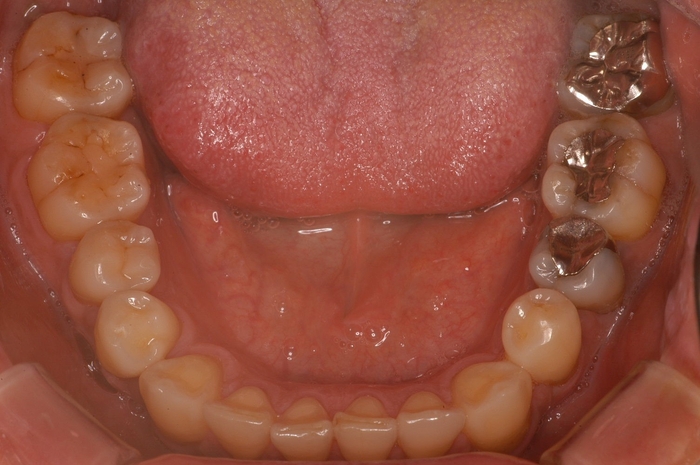

「理想的な歯並び」と「現代人に多い歯並び」の画像、これは何を意味しているのか?